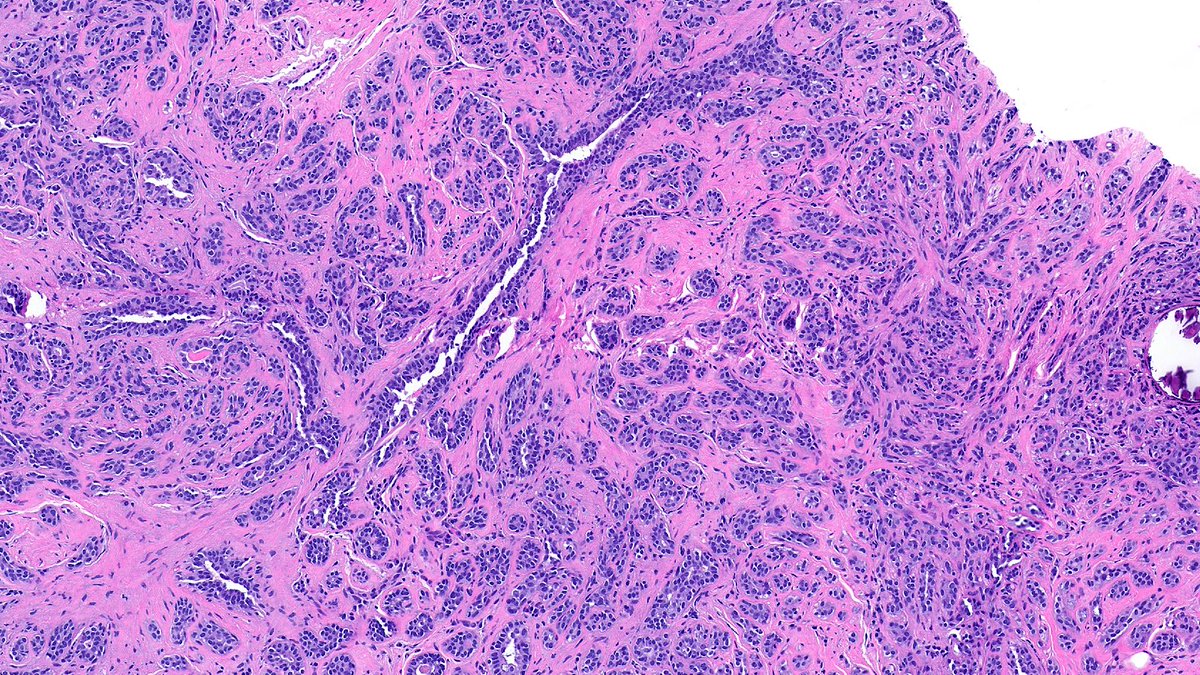

Nasal mass in young male #ENTPath #PathX What is your differential diagnosis? Which stain(s) are confirmatory? @Pathoutlines @UMichPath

MeredithKHerman's tweet image. Nasal mass in young male #ENTPath #PathX

What is your differential diagnosis?

Which stain(s) are confirmatory?